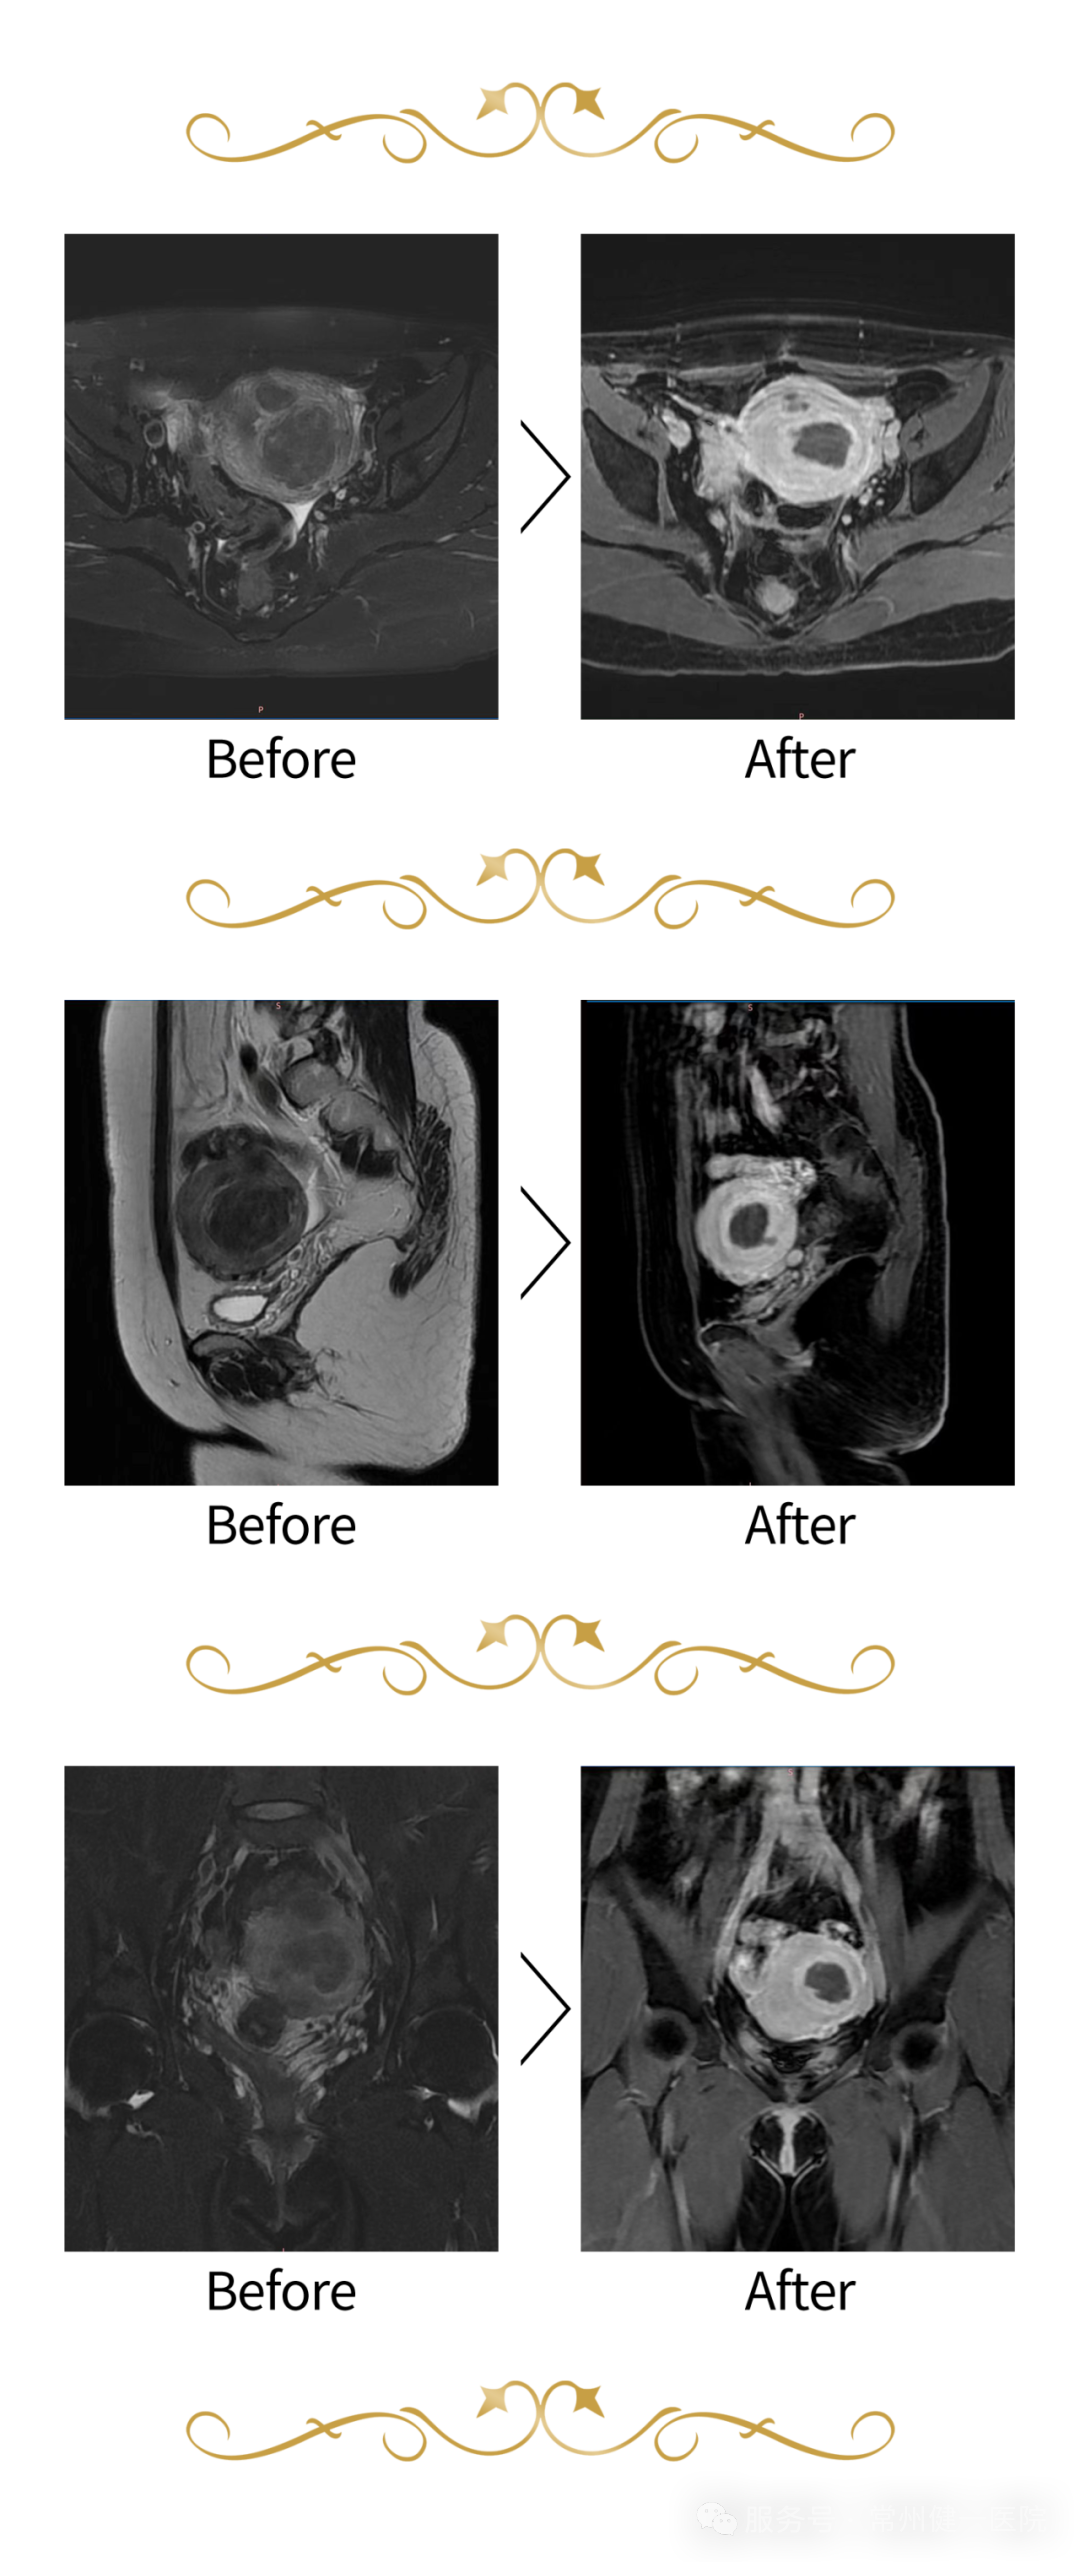

注釋:患者*前後病竈對(duì)比

—     手術(shù)*時(shí)®β間(jiān)2.5小(xiǎo)時(shí)

—     共規劃實施58個(gè)≈£>✔消融點

—     *後NPV‍" r ~90.79%